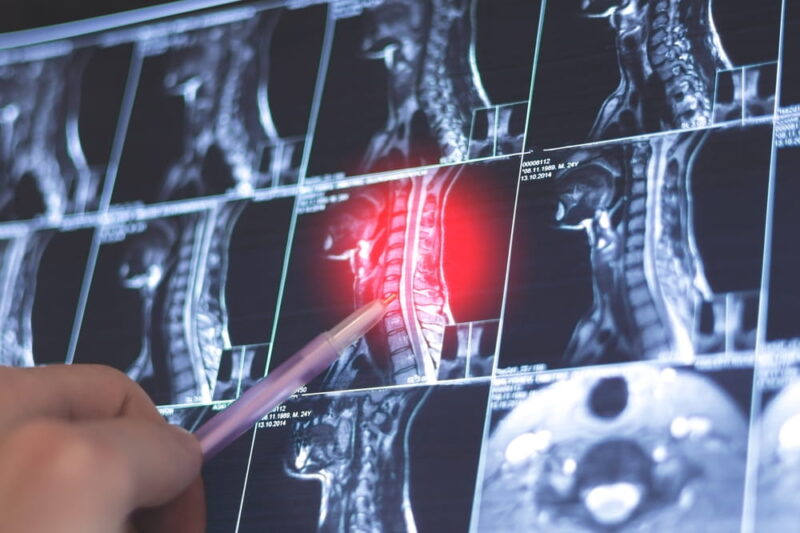

Evaluation typically includes a detailed neurological exam and imaging studies such as an MRI to assess spinal cord compression. MRI provides detailed views of the spinal canal, discs, ligaments, and spinal cord itself.